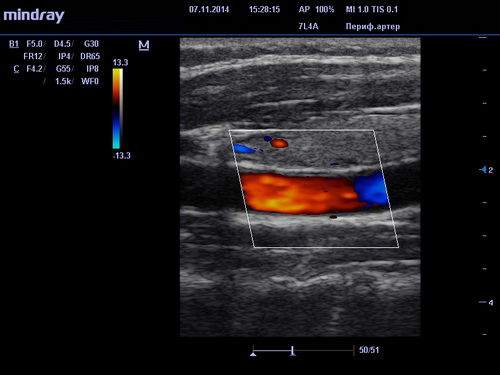

УЗИ сосудов в клиниках DoktorRU проводится по технологии, за основу которой взят эффект Допплера. Его суть заключается в том, что о состоянии и положении объекта можно судить по ширине волны, исходящей от него при движении. Это открытие дало возможность исследовать такие мельчайшие объекты как кровяные тельца в движении. УЗИ сосудов при использовании допплерометрии (или как ее еще называют, Допплерографии) позволяет получать очень точную информацию о состоянии кровеносных сосудов и на ее основе выявлять заболевания даже на ранних, досимптомных стадиях. Поэтому УЗИ сосудов объективно можно считать важнейшим инструментом диагностики и профилактики сердечно-сосудистых заболеваний.